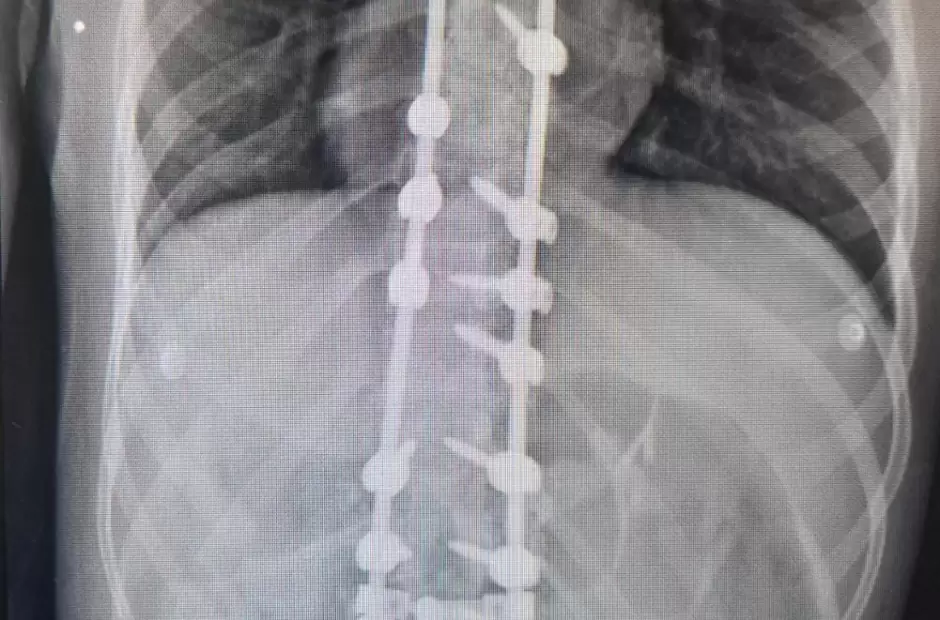

Al igual que en la anterior oportunidad, la intervención fue un trabajo conjunto con el Hospital de Niños, dado que la paciente tiene 17 años. Según informaron, esta padecía una malformación congénita, habiendo iniciado su tratamiento en el nosocomio infantil y para luego ser operada en el “San Juan Bautista”. En tanto ela cirugía, que tuvo una duración de más de 4 horas de quirófano, se logró la reducción de la deformación dorsolumbar mediante la colocación de barras y tornillos pediculares.